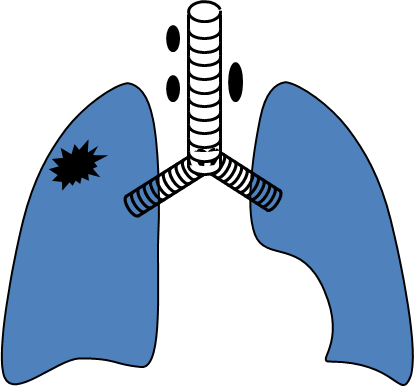

Mərhələnin təyini

Ağciyər xərçənginin mərhələsini təyin etmək üçün törəmənin ölçüsünü, mediastinal strukturlara, limfa düyünlərinə və uzaq orqanlara yayılmanı yoxlamaq lazımdır:

- Mediastinal strukturlara yayılmanı dəqiqləşdirmək üçün KT və endobronxial USM ilk seçimdir (Şəkil 11).

- Mediastinal limfa düyünlərinə yayılmanı qiymətləndirmək üçün əvvəllər mediastinoskopiya çox istifadə edilirdi, hazırda endobronxial USM və PET-KT geniş tətbiq edilməyə başlamışdır.

- Uzaq metastazaları təyin etmək üçün ilk növbədə abdominal KT (böyrəküstü vəzə və qaraciyərə yayılmanı qiymətləndirmə) edilir, sümüklərə və beyinə metastazı yoxlamaq üçün PET-KT tətbiq edilir.

- Mərhələnin dəqiq təyini, xüsusən də, yerli yayılma dərəcəsi əsasən əməliyyat vaxtı müəyyənləşdirilir.

Şəkil 11. Ağciyər xərçənginin diaqnostikası (KT).